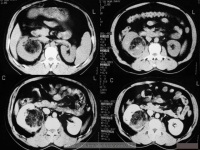

肾移植CT